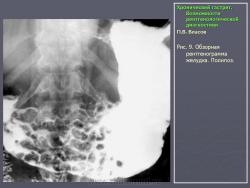

По их мнению, это состояние очень характерно для язвенной болезни и представляет собой тот язвенный фон, на котором развивается язва. Если в подобном стрессовом состоянии поддерживать желудок длительное время, оно может перейти в истинный гастрит. На рис. 7 представлено одно из наших наблюдений диффузной гиперплазии слизистой желудка при хронической язве двенадцатиперстной кишки. Особую форму паренхиматозной гипертрофии слизистой представляет так называемая болезнь Менетрие. Истинная болезнь Менетрие встречается очень редко. Это состояние так же, как и при язвенной болезни, характеризуется выраженной диффузной железистой гипертрофией слизистой оболочки. Толщина слизистой при этом увеличивается в несколько раз. Увеличивается и ее площадь, вследствие чего складки становятся толстыми и извилистыми, поверхность их приобретает зернистый вид. В целом картина напоминает мозговые извилины. Изменения обычно ограничиваются областью тела желудка. При гистологическом исследовании наблюдается глубокая метаплазия железистого эпителия. Нормальные дифференцированные клетки желез замещаются низкодифференцированным эпителием покровного типа. Желудочные ямки при этом резко углубляются, в связи с чем на гистологических срезах слизистая оболочка приобретает вид ворсинчатых разрастаний. Вследствие потери дифференцировки железистого эпителия развивается ахлоргидрия и ахилия. Воспалительная инфильтрация стромы слизистой либо отсутствует, либо выражена незначительно. Строма выражена слабо. Все это свидетельствует о том, что данное состояние не соответствует известным критериям воспаления. В рентгенологическом изображении подобное избыточное развитие слизистой формирует картину, которая напоминает рак. Однако в отличие от злокачественной опухоли желудок не только не уменьшен, но даже увеличен в размерах. Стенки желудка и складки слизистой сохраняют эластичность и нормальную перистальтику. В отличие от распространенного гастрита отсутствует гиперсекреция. На рис. 8 представлено одно из наших наблюдений болезни Менетрие. Особо стоит вопрос с понятием “полипозный гастрит”. Сюда не следует относить одиночные или множественные полипы. На наш взгляд, они к гастриту не имеют никакого отношения. Это особое состояние, которое следует рассматривать как онкологическую и хирургическую проблему. В какой-то мере близко к гастриту стоит стелющийся полипоз желудка, при котором вся или значительная часть выходного отдела желудка покрыта клумбообразными аденоматозными разрастаниями. В литературе они называются “стелющийся аденоматоз”. Подобные состояния встречаются исключительно редко, они также относятся к области онкологии и, на наш взгляд, в рубрике гастритов не должны рассматриваться. К гастритам нередко относят полипоз желудка. Следует различать несколько состояний, сопровождающихся пролиферацией слизистой полипоидного характера. Своеобразным состоянием является диффузная пролиферация с гистологическим строением, характерным для полипов, где полностью отсутствуют высокодифференцированные железистые комплексы. Возможно, в их основе лежит хроническое воспаление. Вместе с тем существует полипоз желудка врожденного генеза, нередко сочетающийся с полипозом кишечника (например, семейный полипоз). Совершенно иное происхождение имеют множественные полипы, располагающиеся на фоне практически не измененной слизистой оболочки, их нельзя относить к гастриту. На рис. 9 приведено одно из наших наблюдений полипоза желудка, не связанного с гастритом. Несостоятельным, по нашему мнению, является деление гастритов по характеру секреции. Распространенные в недавние времена такие понятия, как анацидный, гиперацидный и нормацидный гастриты, по современным представлениям являются неправомерными. Большой вклад в утверждение идеи независимости уровня кислотности от гастрита, а соответственно от морфологического состояния слизистой оболочки внесли европейские ученые M. Einhorn, W. Leube, американские ученые M.W. Comfort и F.R. Vanzant, а также наши отечественные клиницисты М.П. Кончаловский, А.С. Белоусов и др. Перечисленные авторы убедительно доказали, что различные уровни кислотности, включая ахлоргидрию, являются конституциональными вариантами, отражают порог нейрогуморальной возбудимости железистого аппарата слизистой и не имеют под собой определяемой современными методами морфологической основы.

Все возможные варианты перестройки рельефа слизистой оболочки, наблюдающиеся при хроническом распространенном гастрите, при хроническом антральном гастрите выражены в большей степени. Определяется расширение и извитость складок в антральном отделе, частым симптомом при антральном гастрите является равномерная зубчатость по большой кривизне – "симптом пилы". Одной из разновидностей антрального гастрита является так называемый гранулярный гаст­рит, характеризующийся своеобразным "сосочковым" рельефом внутренней поверхности желудка.

Рентгенологическая картина заболевания включает все ха­рактерные функциональные симптомы хронического гастрита: на­личие в желудке жидкости, слизи, изменения тонуса и перисталь­тики, а также морфологические признаки, проявляющиеся разно­образной перестройкой рельефа слизистой оболочки. На фоне измененных или нормального калибра складок слизистой оболоч­ки, а также в бороздах беспорядочно располагаются мелкие, нечетко очерченные дефекты на рельефе не­правильной формы. Эти изменения всегда локализуются в антральном отделе, и нередко распространяются на другие отделы желудка. Размер полипозных разрастаний, как правило не превышает 5 мм, контуры нечеткие, в межскладочных пространствах их может быть не видно. Полипозный гастрит необходимо дифференцировать от полипоза желудка, при котором отсутствуют функциональные изменения и не видны складки слизистой оболочки; аденоматозных полипов и аденопапилломатоза.